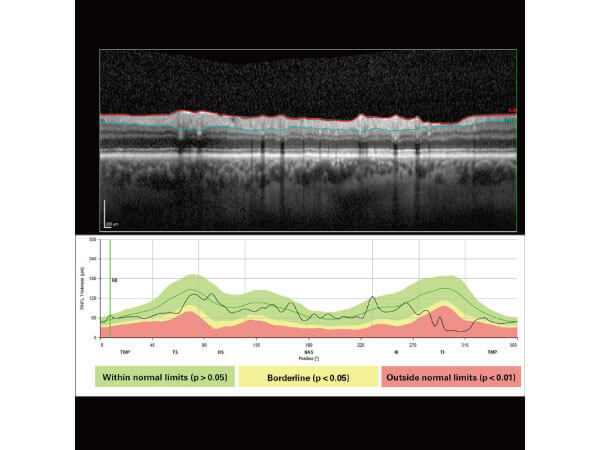

醫療設施:OCT眼底光學斷層掃描

高解析度眼底光學斷層掃描,老年性黃斑部病變、糖尿病黃斑部水腫、高度近視黃斑部病變、青光眼視神經纖維層厚度掃描。

醫療設施:青光眼視神經纖維層厚度掃描

青光眼初期篩檢,青光眼視神經構造退化速度系列追蹤。